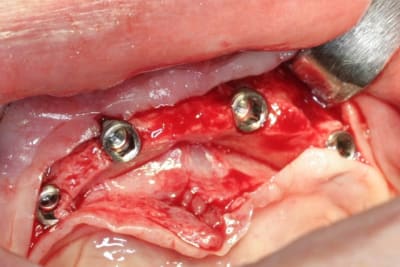

barre pour stabilisation du complet bas...;-)

le patient, niveau budget pouvait se permettre mieux...on aurait pu faire sans problème un all on six (ou plus) transvissé...si son état de santé avait été meilleur...pas très grave...mais son Parkinson lui complique l'hygiène buccale...alors passer des brossettes loin au fond...là au moins son épouse pourra l'aider...çà sera pas trop compliqué...et au niveau confort, c'est quand même pas mal...

mais le ptit plus de cette intervention...c'est pas les mêmes implants que d'hab...c'est des drive implant...pas mal du tout...du moins pour la chir...

forets super...avec butées clipsables (très pratique et sécurisant), super stab primaire...très sympa...

ah, celle là, je l'attendais...c'est court parce qu'il y a, après étude du scan...un gros, très gros canal incisif qui passe juste dessous...et qui donne un foramen mentonnier dans la zone antérieur...bien identifié...du genre à contenir un faisceau sensitif pour le menton et la partie médiane de la lèvre...tu vois ce que je veux dire...???

pour ce cas, j'ai posé en 34 et 44 des 4x8...et pour 32 et 42 des 4x10...

pour répondre à une autre de tes questions..."pourquoi pas les expanseurs"...simple...la bourde...l'assistante qui oublie de les mettre à stériliser...mais bon y manque pas grand chose en vestibulaire...et c'est aussi pourquoi j'ai mis des 4mm en 34 et 44...à l'origine je voulais mettre des 5mm...